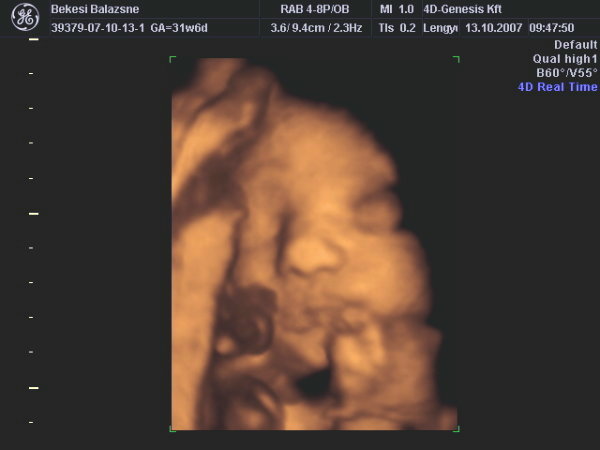

A második képen nyitva van a szeme is